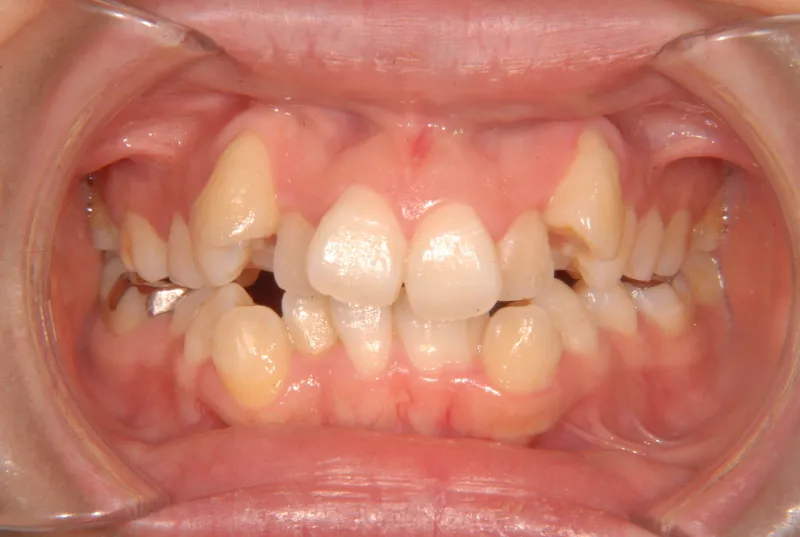

治療終了後

治療前と治療後で下の歯の銀歯がなくなっています。

これは銀歯の第1大臼歯を抜いて第2大臼歯、第3大臼歯の親知らずを使いました。

コルチコトミーという矯正法で歯根への負担を軽減しながら治療しました。

治療回数71回、3年5ヶ月の治療期間で矯正治療を終了しました。

主訴が改善され、ご満足頂きました。